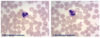

Sickle Cell Erythrocytes

Normal RBCs